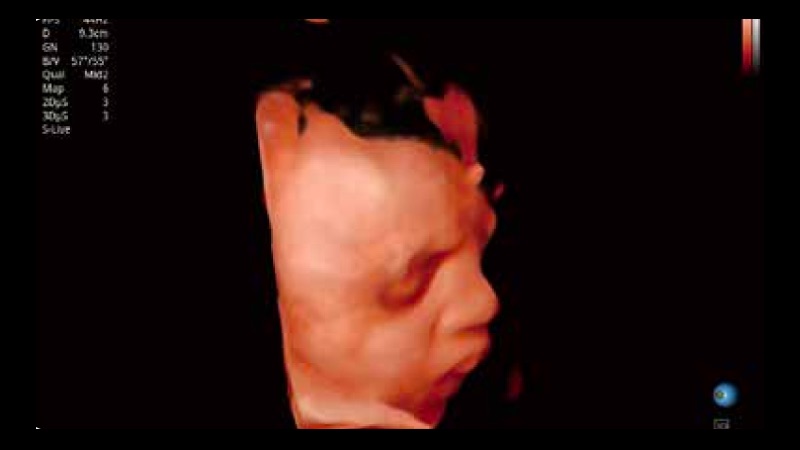

容积探头

凭借公海贵宾会员检测中心医疗先进的成像技术和优异的探头技术提供的清晰的图像表现,您可以更自信地做出临床决策。